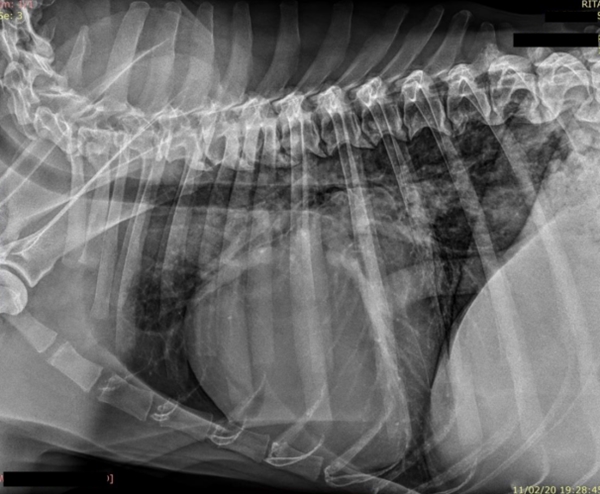

Tras el proceso de estabilizar el distrés respiratorio que presentaba, se realiza estudio radiográfico del tórax

Y se recomienda: